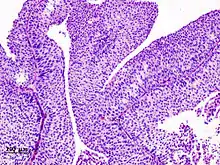

Histopathology of urothelial carcinoma of the urinary bladder. Transurethral biopsy. H&E stain

Non-papillary carcinoma includes carcinoma in situ (CIS), microinvasive carcinoma and frankly invasive carcinoma.[68] Carcinoma in situ (CIS) invariably consists of cytologically high-grade tumour cells.[69]

Transitional cell carcinoma can undergo differentiation (25%) into its variants.[68][70][71] When seen under a microscope, papillary transitional cell carcinoma can present in its typical form or as one of its variations (squamous, glandular differentiation or micropapillary variant). Different variations of non-papillary transitional cell carcinoma are listed below.